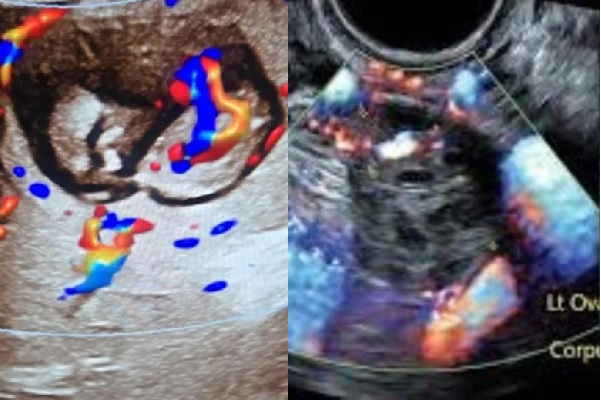

உத்தரப் பிரதேச பெண்ணின் கல்லீரலில் கரு வளர்வது கண்டுபிடிப்பு ; மருத்துவர்கள் அதிர்ச்சி

உத்தரபிரதேசத்தில் ஒரு பெண்ணின் கருப்பைக்கு பதிலாக கல்லீரலில் கரு வளர்வது கண்டறியப்பட்டது. புலந்த்ஷாஹரில், மருத்துவர்கள் தங்கள் வாழ்க்கையில் முதல் முறையாக இதைப் பார்த்து திகைத்துப் போனார்கள், இது…